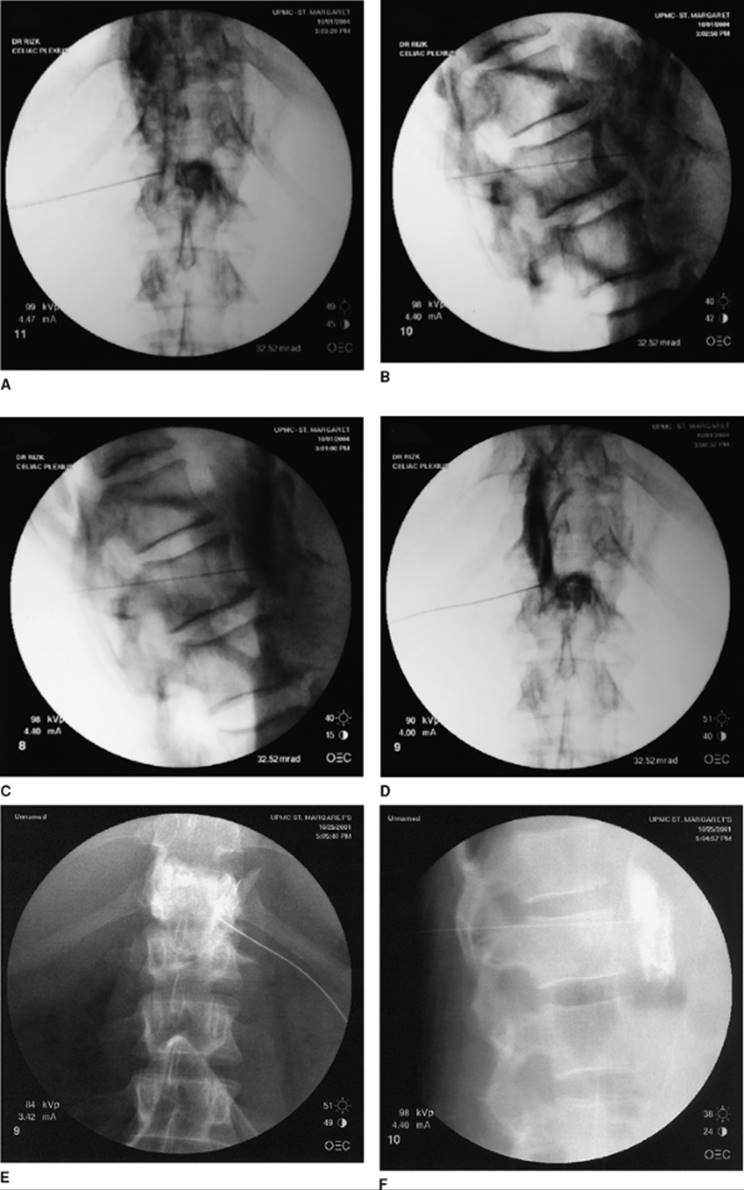

Approach and Technique: Fluoroscopy is used to take an anterior–posterior (AP) view and mark the T12-L1 junction (Fig. 63-4A). The beam is oblique to hide the ipsilateral transverse process (left side) behind the shadow of the upper third of the L1 vertebral body. A slight cephalad–caudad tilt of the beam may be necessary to square the endplates. This point should be marked and is approximately 6–8 cm from midline. After skin wheal and deep infiltration of local anesthetics, advance the needle parallel to the x-ray beam. Of great importance is taking frequent AP views to assess needle direction and lateral views (Fig. 63-4B) to assess depth. Once the anterior third of the vertebral body is reached, the stylet is removed from the needle and 0.1 cc–0.2 cc of PFNS is injected to occupy the needle and prevent air embolization. Once the aorta is pierced, very gentle aspiration is continuously applied until negative aspiration for blood. Advance 2–3 mm. Inject a small amount of the dye. Injection should be very slow and you should not feel any resistance. Resistance to injection may indicate injection in the wall of the aorta and may cause dissection. Injection of the local anesthetic should commence after desirable AP (Figs. 63-4D and E) and lateral (Figs. 63-4C and F) views are obtained with adequate propagation of the dye without intravascular runoff. Following the local anesthetic, absolute alcohol is injected slowly. Needle tip is about 1½ -2cm anterior to the vertebral body. The same is done on the right side, stopping just anterior to the vertebral body.

Figure 63-4. A: Needle position at T12-L1 AP view. B: Lateral view. C and F: Lateral view with contrast. D and E: AP view with contrast.